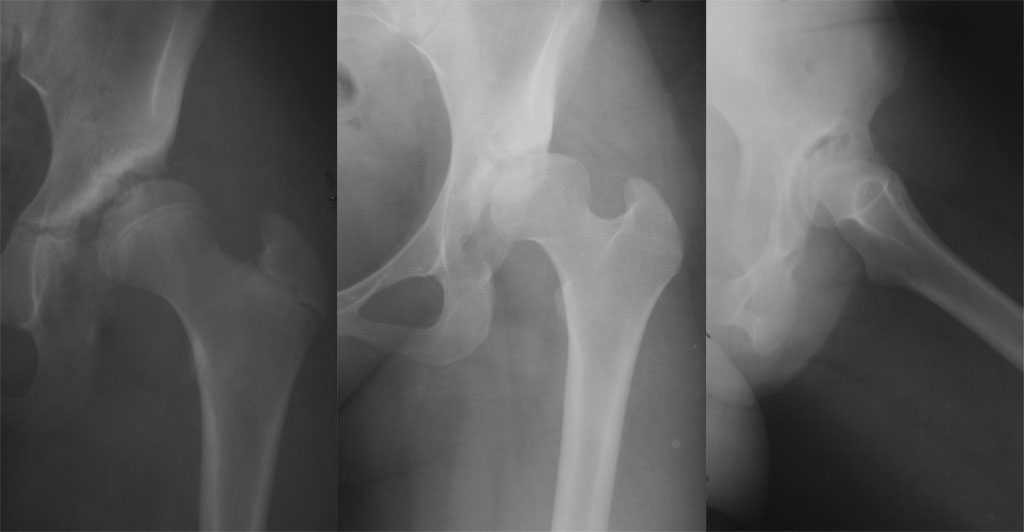

[Ortho] Фиброзная дисплазия подвздошной кости

Как раз к обсуждению. Обратилась за косультацией 21-летняя девушка с жалобами на боли в левом тазобедренном суставе. Что можно ей порекомендовать?